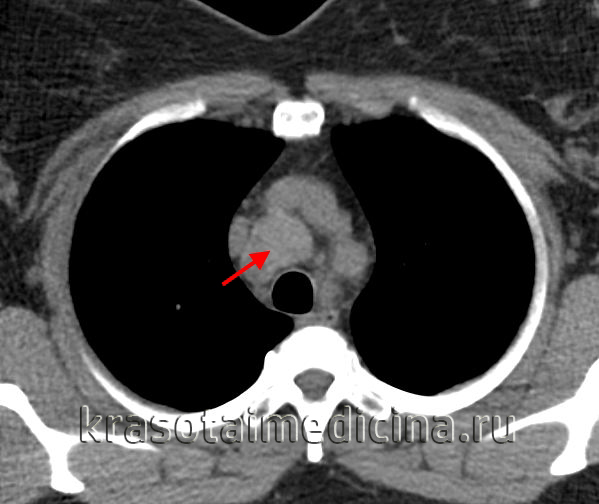

Лимфомы медиастинальной локализации не всегда диагностируются при рентгенологическом обследовании. Компьютерная томография, более детально, чем обзорная рентгенография позволяет рассмотреть конгломерат опухоли, увеличение лимфоузлов средостения, вовлечение паратрахеальных, трахеобронхиальных, прикорневых лимфатических узлов. Диагностическая значимость магнитно-резонансной томографии в верификации лимфом средостения признается не всеми авторами.

КТ ОГК. Объемное образование в средостении (патологически измененный лимфоузел), подтвержденная лимфома.